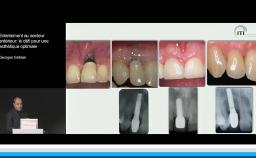

Cette présentation s’intéresse à l’influence des étapes chirurgicales sur le résultat esthétique en implantologie.

Il est communément admis qu’une épaisseur minimale de gencive kératinisée autour des implants est favorable au résultat esthétique mais aussi au maintien d’une bonne santé des tissus péri-implantaires au long terme, mais il n’existe pas de consensus à ce niveau. Une épaisseur osseuse de 2 mm autour des implants est nécessaire pour prévenir les résorptions osseuses et pour soutenir de façon pérenne les tissus mous.

Tous les types d’implants peuvent être utilisés en secteur antérieur, mais l’utilisation de connexions au niveau osseux offre plus de latitude sur le placement de l’implant et sur la réhabilitation prothétique. Afin de limiter les proximités entre implants et entre dents et implants, l’utilisation d’implants de faible diamètre et la réduction du nombre d’implants sont des options à considérer.